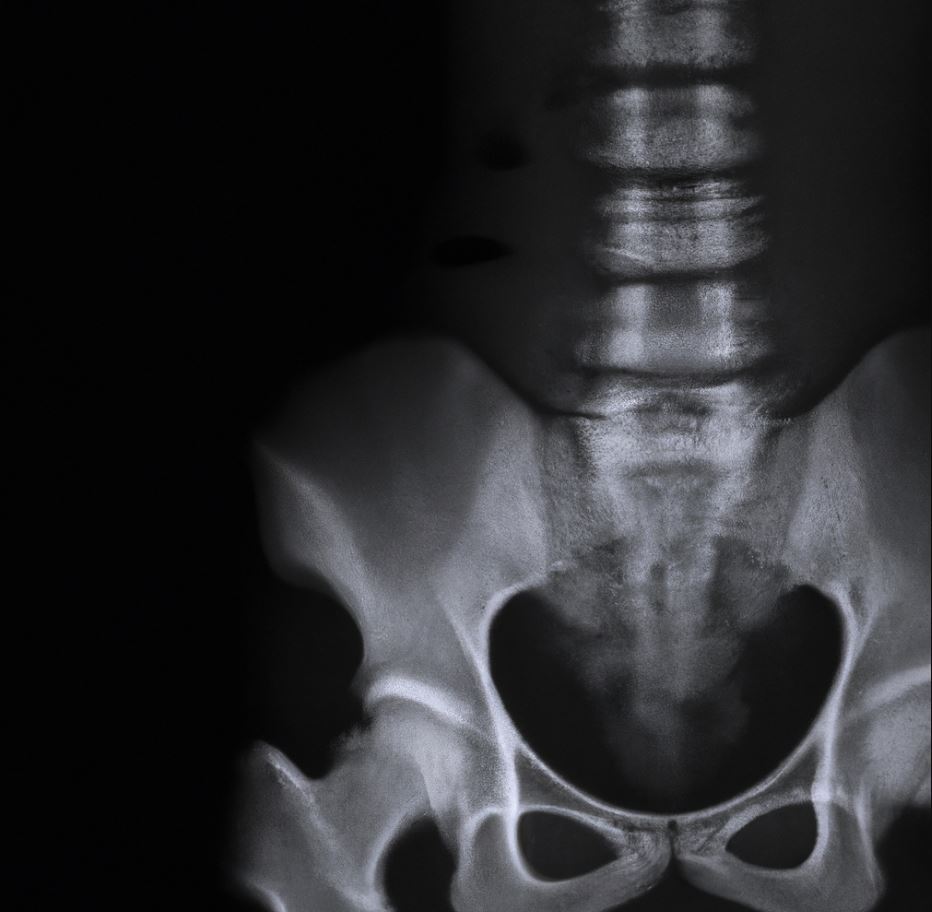

골다공증은 뼈의 밀도가 감소하여 뼈가 취약해지는 질환입니다. 이러한 상태를 예방하고 개선하기 위해서는 올바른 식습관을 유지하는 것이 중요합니다. 아래는 골다공증을 예방하기 위한 식습관에 대한 일반적인 지침입니다.